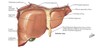

NAVL of liver

N: hepatic N plexus: SNS from celiac plexus, PNS from vagus

A: portal vein (70%), hepatic (30%)

V: 3 formed by union of central veins –> drain to IVC inferior to diaphragm

L: hepatic –> celiac –> cisterna chyli

Subphrenic (Suprahepatic) Recess

pocket b/w diaphragm and anterior/superior part of liver

separated into right and left recesses by the falciform ligament.

functional “left liver” inclues

L lobe, caudate, quadrate lobes